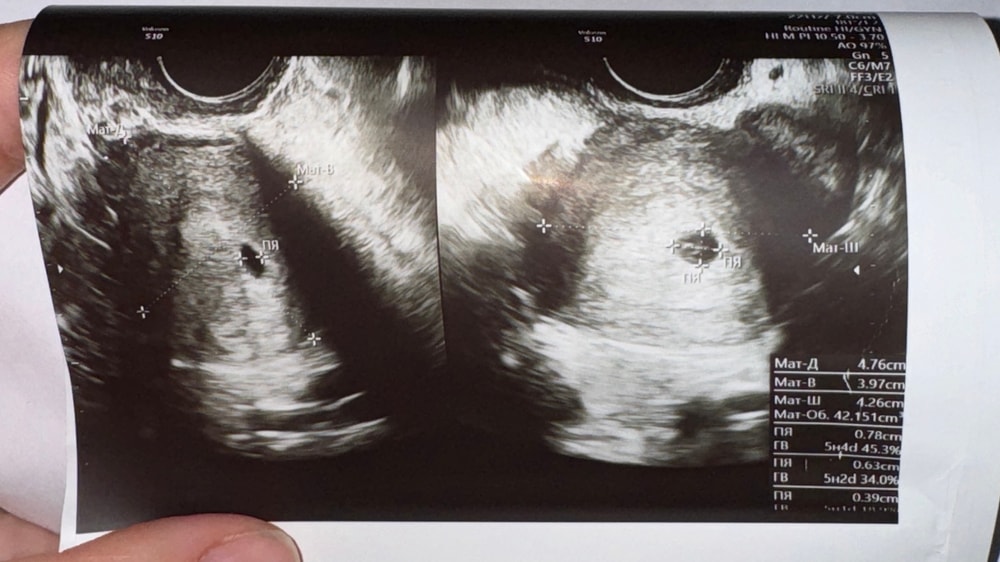

Первое УЗИ в 5н3д

сделала первое узи 😍 малыш в матке, виден желтый мешочек, идем в срок 🥰